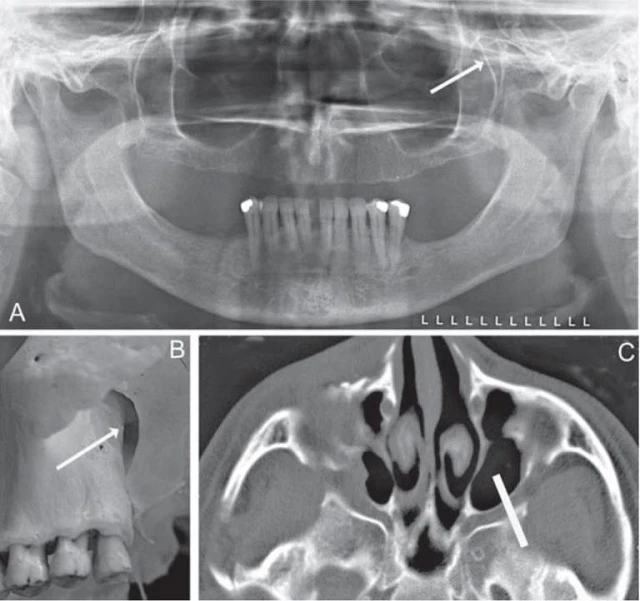

Hình 20. Xương hàm trên hoặc tầng giữa mặt, cấu trúc giải phẫu xương trên phim x-quang toàn cảnh. Hình A (có đánh số) và hình B (không đánh số) là những bản sao của cùng một bệnh nhân. 1, Lồi khớp, xương thái dương. 2, Xương gò má. 3, Mấu gò má xương hàm trên. 4, Rãnh bướm hàm. 5, Sàn ổ mắt. 6, Mặt trước của xoăn mũi dưới. 7, Vách mũi. 8, Gai mũi trước. 9, Sàn xoang hàm trên. 10, Răng cối lớn thứ ba hàm trên bên trái (đang mọc). 11, Thuỳ tai. 12, Thân đốt sống cổ.